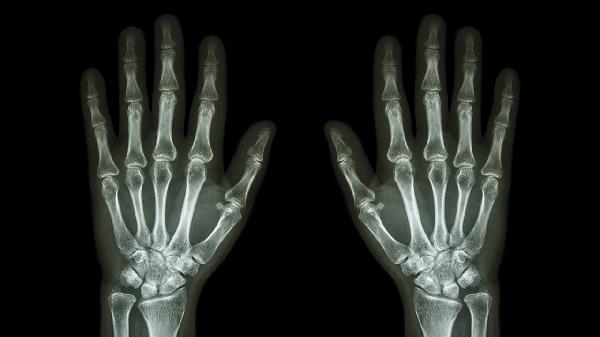

手指关节受到外力撞击或扭伤可能导致局部软组织损伤,表现为红肿、疼痛和活动受限。轻微外伤可通过冷敷缓解肿胀,48小时后改为热敷促进血液循环。若伴随明显淤血或关节变形,需排除骨折可能,建议拍摄X线片明确诊断。